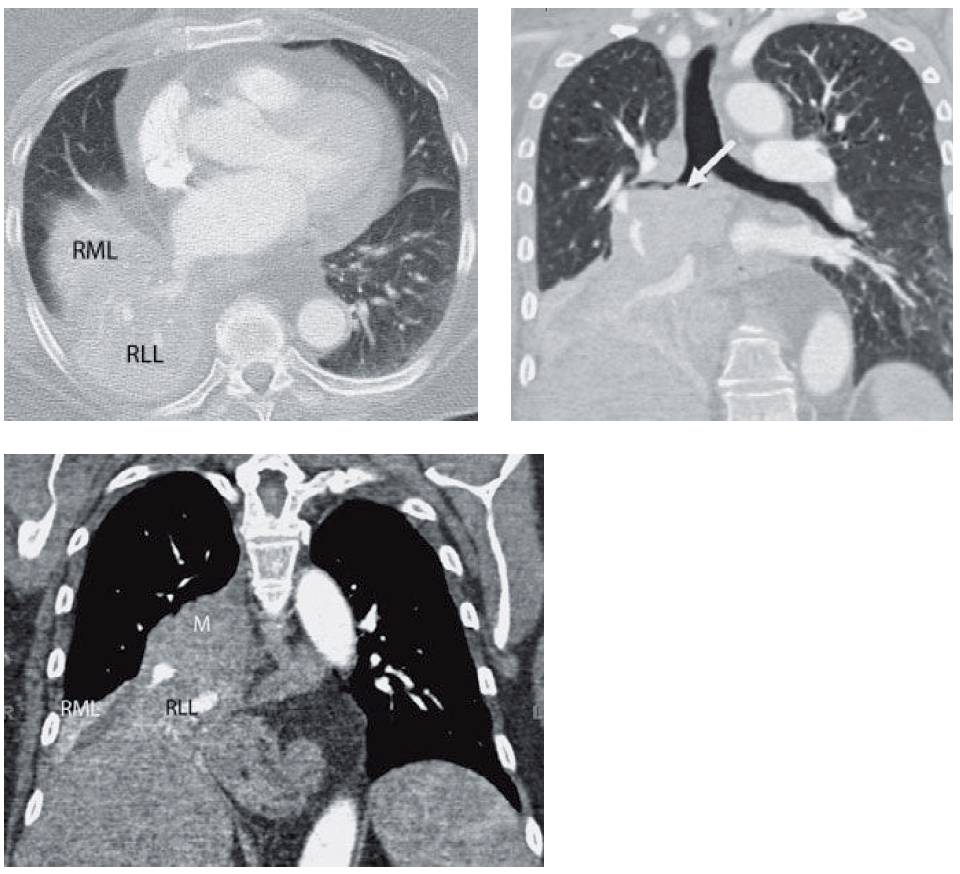

- CT was performed the next day, which showed the collapsed lobes (RML = middle lobe and RLL = right lower lobe). Reconstructions more clearly delineate the central mass (white arrow) and the collapsed lobes (RML = middle lobe, RLL = lower lobe, and m = mass).

Based on the radiograph, right middle lobe and right lower lobe collapse should be the main consideration.

- Right middle and lower lobe collapse is the result of obstruction of the bronchus intermedius, from either mucus or an endobronchial lesion.

- The volume loss of both lobes results in inferior displacement of the minor and major fissures. Usually, the minor fissure falls below the level of the major fissure and the major fissure extends superiorly to the hilum. The net composite is the “S-shaped” opacity as seen above, especially when a central mass is present.

- Right middle and lower lobe collapse displaces the right hilum inferiorly and obscures the descending right interlobar artery.

- Shift of the heart and mediastinum rightward is frequently seen with this combination of collapse.

- To prevent confusion with a right pleural effusion, one must remember that an effusion is higher laterally and combined right middle and lower lobe collapse is higher medially.